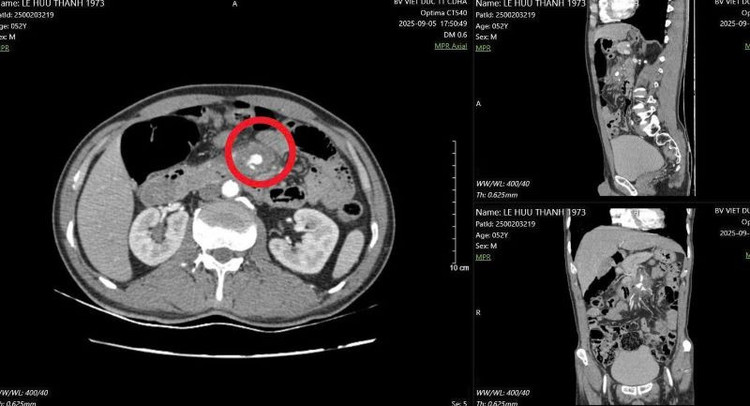

Hình ảnh đoạn D3 tá tràng tổn thương, cạnh động mạch mạc treo tràng trên - Ảnh BVCC

Nguy hiểm hơn, đầu tăm tiếp tục đâm vào một trong những mạch máu lớn nhất trong ổ bụng – động mạch mạc treo tràng trên, là nơi đưa máu nuôi phần lớn ruột non. Tổn thương này đã khiến thành mạch máu bị phồng lên giả tạo (gọi là “giả phình mạch”), nếu không được phát hiện và xử trí kịp thời có thể gây vỡ mạch, chảy máu ồ ạt trong ổ bụng, đe dọa tính mạng.

Đây là tình huống hiếm gặp nhưng vô cùng nguy hiểm, đe dọa trực tiếp đến tính mạng người bệnh nếu không được cấp cứu kịp thời. Đồng thời việc xử trí tổn thương đường tiêu hóa kết hợp với mạch máu cũng hết sức phức tạp.